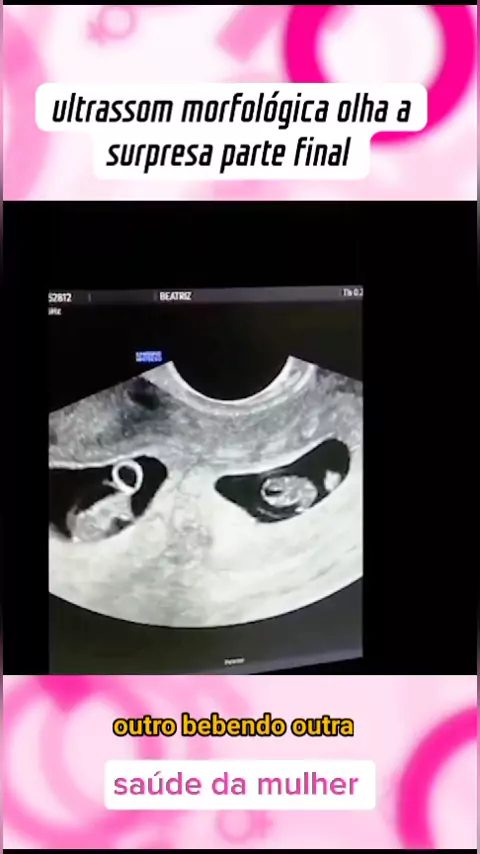

Saúde feminina

ultrassom de gêmeos #medico #medicina #Saúde #viraliza